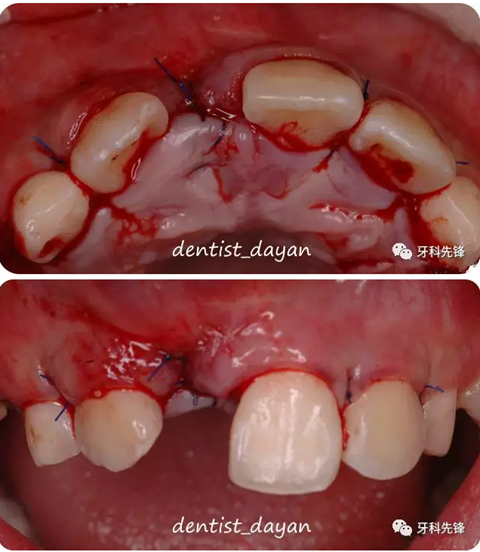

翻瓣,可見12,21之間的多生牙,陸續(xù)將多生牙拔除。

拔牙術(shù)后數(shù)周。